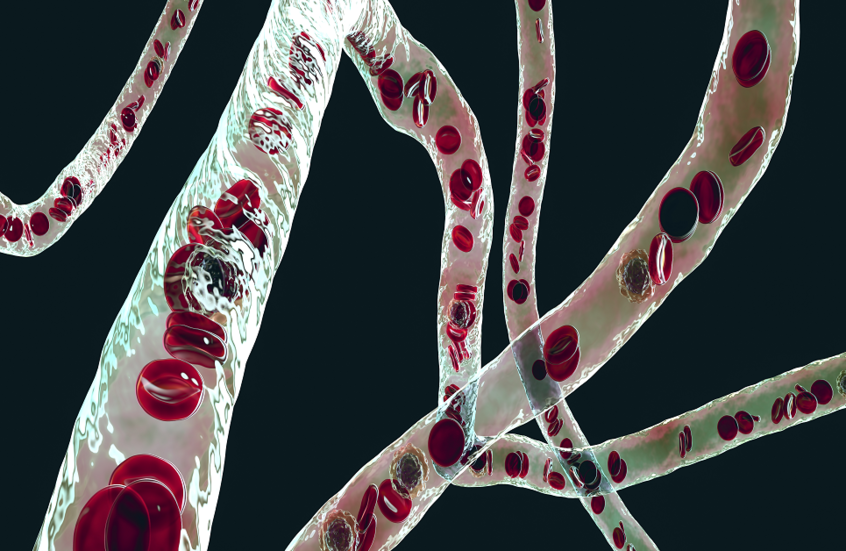

يمكن لأعراض نوبة القلب أن ترسل موجات صدمة عبر جسمك، ما يتسبب في ظهور الأعراض في أماكن مفاجئة.

وتعد النوبة القلبية حالة طبية طارئة خطيرة حيث يتم منع إمداد القلب بالدم فجأة، عادة بسبب جلطة دموية. ونظرا لموقعه، فإن ألم الصدر يعتبر السمة المميزة للأزمة القلبية. وكما أوضح الطبيب العام، ألكا باتيل، لموقع "إكسبريس": "في المجال الطبي، كان الوصف الكلاسيكي للنوبة القلبية دائما "ألما مركزيا ساحقا في الصدر".

ومع ذلك، فإن التركيز فقط على ألم الصدر لا يعكس النطاق الكامل للأعراض المحتملة، ويمكن أن يكون له عواقب وخيمة.

وكشف باتيل أن هناك مواقع رئيسية أخرى في جسمك يمكن أن تشير أيضا إلى نوبة قلبية. وحذر من أن منطقة المعدة هي أحد أكبر ضحايا النوبات القلبية.

وقال: "عندما تموت عضلة القلب بسبب نقص الأكسجين، تطلق الأنسجة المصابة مجموعة من المستقلبات، بما في ذلك حمض اللاكتيك، الذي يحفز الألياف العصبية التي تسبب الغثيان والقيء".

أعراض محتملة غير معروفة للإصابة بالنوبة القلبية

وأضاف أن "العصب المبهم الطويل" الذي يتجه إلى القناة الهضمية، يرتبط أيضا بالقلب، وهذا ما يتهيج أثناء الأزمة القلبية.

وقال باتيل: "إذا كنت تعاني من قيء غير مبرر، أو غثيان مستمر، خاصة عند إجهاد نفسك، فقد تكون هذه إشارة إنذار".

ويعد تعرق راحة اليد من الأعراض المدهشة الأخرى المرتبطة بنوبة قلبية.

وأوضح الدكتور باتيل: "يتعرق الجسم لإبقاء درجة حرارة الجسم منخفضة؛ إذا كان على قلبك أن يعمل بجهد أكبر لضخ الدم عبر الشرايين الضيقة، فسترتفع درجة حرارتك كلما استهلكت المزيد من الطاقة وبالتالي ستتعرق".

وغالبا ما يتجاهل الناس أنهم يعانون من نوبة قلبية ويؤخرون طلب الرعاية الطبية.